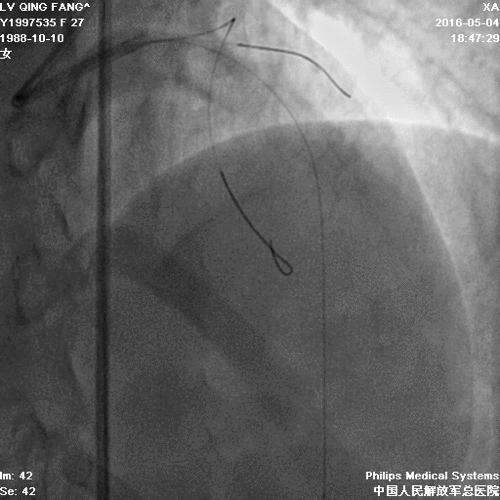

PCI

• 术后患者无心绞痛症状出现,日常体力活动不受影响。